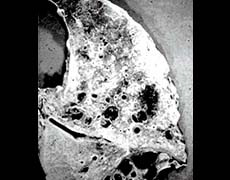

a damaged lung

clogged with thick mucus

a disease called cystic fibrosis

made breathing difficult

caused lung infections